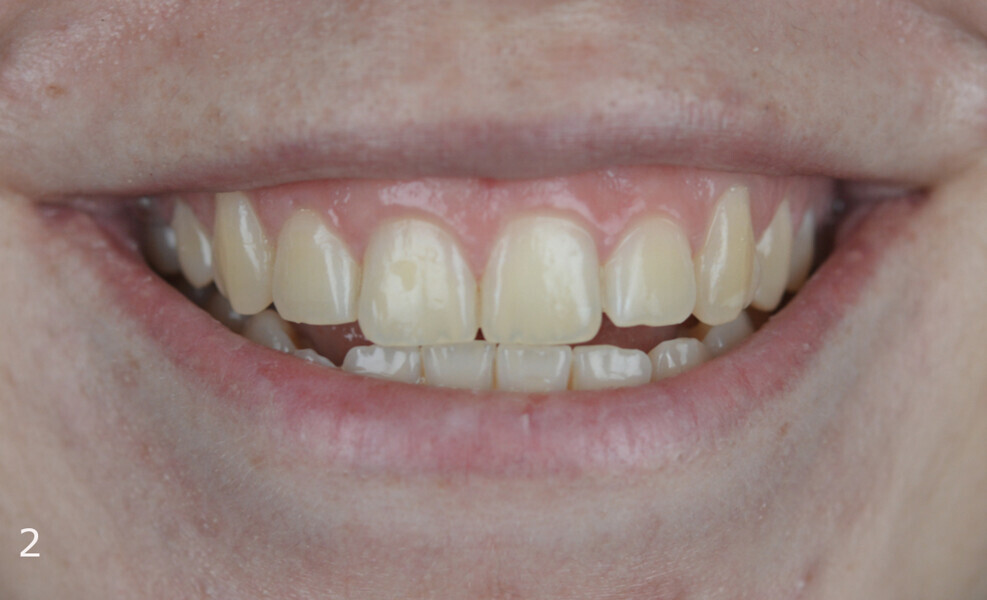

The 23-year-old dolichofacial female patient complained of not being able to chew properly. Facial examination showed a convex profile, an enlarged lower facial height, and a skeletal Class III malocclusion (Figs. 1–3). Intra-oral examination revealed an Angle Class III right subdivision malocclusion, anterior open bite, no overjet and a maxillary dental midline deviated about 3 mm to the right compared with the mandibular dental midline (Fig. 4). The panoramic radiograph confirmed previous extraction of the maxillary right first premolar and the presence of all four third molars (Figs. 5 & 6).